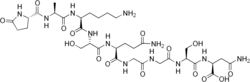

L-Pyroglutamyl-L-alanyl-L-lysyl-L-seryl-L-glutaminyl-glycyl-glycyl-L-seryl-L-asparagine

| C33H54N12O15 | |

| Molar mass | 858.864 g·mol−1 |

Thymulin (also known as thymic factor or its old name facteur thymique serique) is a nonapeptide produced by two distinct epithelial populations in the thymus first described by Bach in 1977.[1] It requires zinc for biological activity. Its peptide sequence is H-Pyr-Ala-Lys-Ser-Gln-Gly-Gly-Ser-Asn-OH.